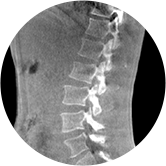

三維脊柱應用

精準診斷

手術方案規劃

術后隨訪

• 脊柱評估

傳統方法都是在二維平面,依靠棘突或椎弓根相對于椎體的偏移來評估脊柱側凸。WR-3D可以更精準評估脊柱側凸,制定手術方案,可以更直觀地顯示和量化椎體的平移和軸向旋轉,術后評估更準確客觀。